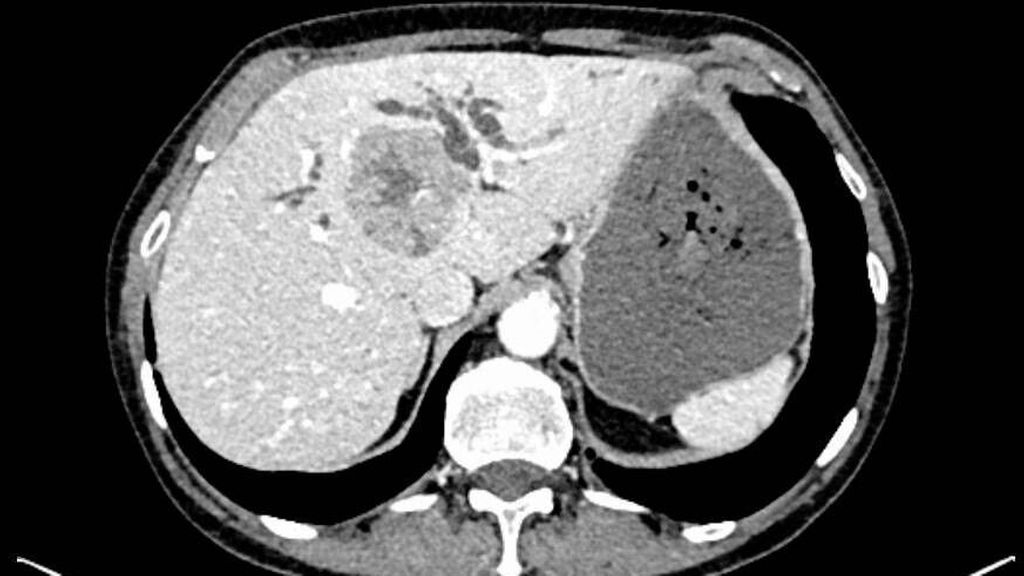

Die initiale CT zeigte eine bis zu 6cm große Raumforderung, ausgehend von der Hepatikusgabel, mit zentraler Infiltration des Leberparenchyms, suspekten Lymphknoten im Leberhilus und retroperitoneal, deutlich dilatierten intrahepatischen Gallengängen sowie Umscheidung und Infiltration des linken Pfortaderastes, jedoch ohne Thrombose. Der Befund war hochverdächtig auf einen cholangiozellulären Tumor. Die histologische Aufarbeitung einer Punktionsbiopsie ergab jedoch ein gering differenziertes, hiläres hepatozelluläres Karzinom (WHO 2019: G3). Angesichts des bildgebenden Befundes und des ebenfalls erhöhten Ca19-9 stand der Verdacht auf einen Mischtumor im Raum.

In der durchgeführten Staging-CT zeigte sich ein partielles Ansprechen (PR) mit Tumorgrößenreduktion von 49mm auf 33mm, die Lymphknoten blieben unverändert. Die Tumormarker sanken (AFP: 150, Ca19-9: 65). Aufgrund der persistierenden Diarrhö und des Verdachts auf einen Mischtumor erfolgte eine Umstellung der Therapie auf Cisplatin/Gemcitabin/Bevacizumab, wobei Gemcitabin ab Zyklus 2 wegen Fatigue auf 75% reduziert wurde und Cisplatin ab Zyklus 3 aufgrund von Ototoxizität abgesetzt werden musste. Nach vier Zyklen zeigte die MRT ein weiteres partielles Ansprechen (19×21mm), die Lymphknoten waren unverändert, die Tumormarker normalisierten sich erstmals.

Bildgebend können sich Mischtumoren wie ein HCC-iCCA-Gemisch imponierend darstellen, wie ein typisches HCC oder aber ein typisches iCCA aussehen oder sich unspezifisch darstellen. Bildgebende Hinweise auf Mischtumoren bestehen bei verschiedenartigem Kontrastmittelverhalten innerhalb eines Tumors (im Verlauf zunehmende Anreicherung, Anreicherung mit Wash-out, Anreicherung ohne Wash-out oder Hypovaskularisierung), vaskulärer Invasion und Gallengangsbeziehungen. Die Kombination erhöhter Tumormarker (AFP und Ca19-9) kann einen Hinweis liefern, ist aber nicht beweisend.